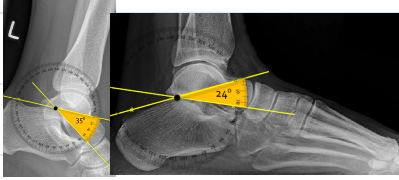

A: Böhler's Angle

assesses the calcaneus for fracture or deformity. The average is 30-35°, with a range of 28-40°. An angle <28° is considered abnormal.